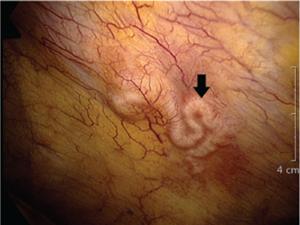

Hình 14. Ấu trùng sán nhái tổn thương ở vùng đỉnh màng phổi qua nội soi ngực

Bệnh sán nhái có thể di chuyển gây kích ứng, khiến bệnh nhân ho khan, không có đờm, giống như hội chứng Loffler, gây thương tổn ở màng phổi và nhu mô phổi.